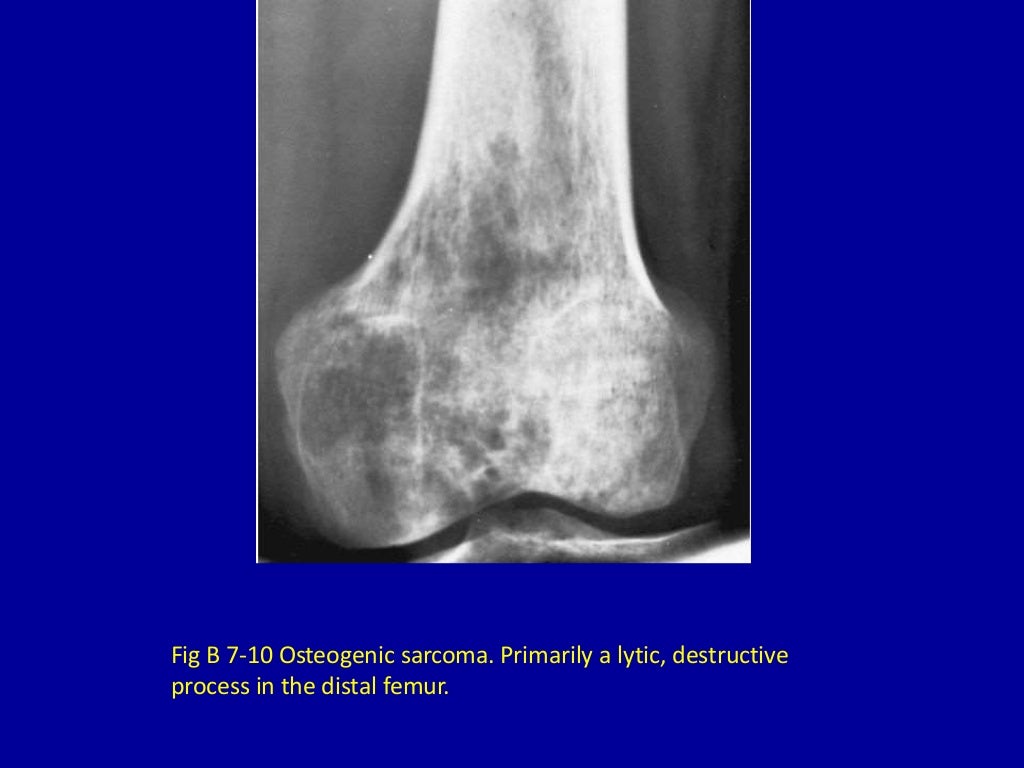

7 moth eaten or punchedout osteolytic destructive lesions of Are Moths Destructive the reality of moth diversity debunking common myths about moths myth: moths, in general, are not physically dangerous to humans. Both of these insects are classified in similar orders (lepidoptera), and most are harmless to. rather, moths turn their backs toward the light at a right angle, causing them to invert their flight or orbit, even. . Are Moths Destructive.